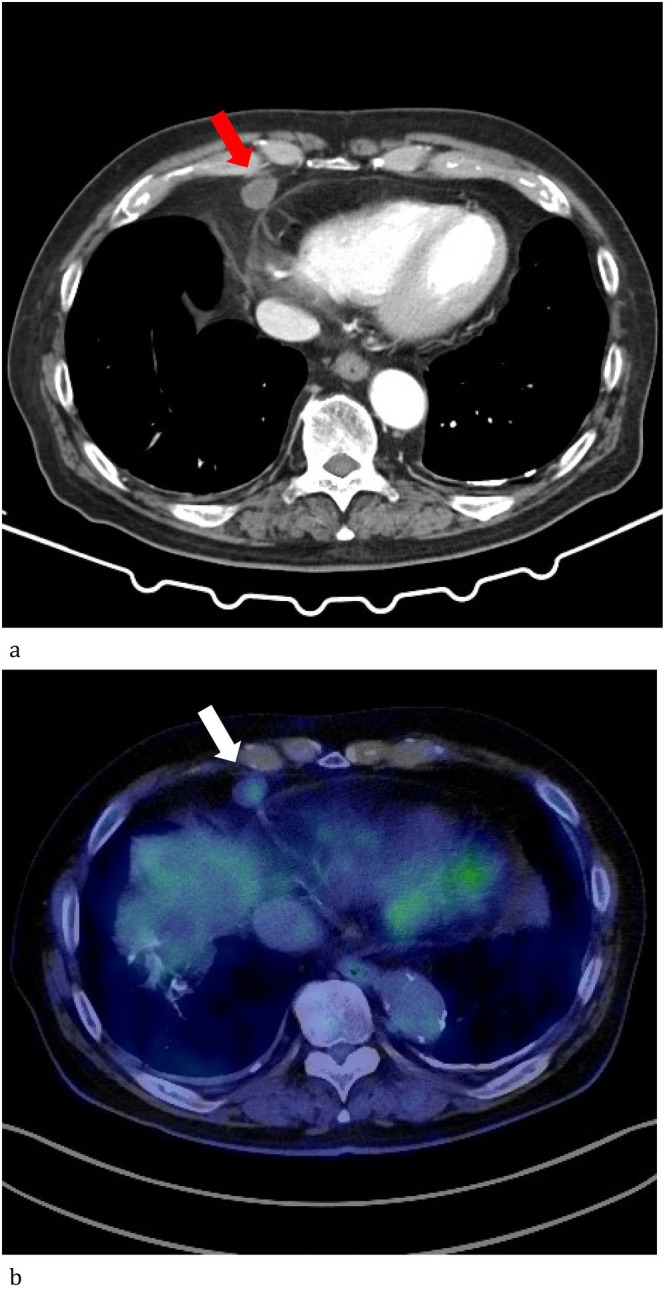

Mesothelial-cell inclusion (MCI) is an inclusion of mesothelial cells found in lymph nodes. Although it is a rare condition, differentiating it from lymph node metastasis is essential to avoid a misdiagnosis. We reported, for the first time, a case of MCI after lung cancer surgery. The patient was a 76-year-old Japanese man with a history of bilateral radical surgery for lung cancer. Follow-up computed tomography performed at 7 years after the initial surgery revealed an enlarged right cardiophrenic angle lymph node. It was resected through video-assisted thoracic surgery, and histopathology revealed non-dysplastic ductal proliferation. Immunohistochemistry was positive for AE1/3, D2-40, calretinin, and WT-1, and negative for CD31, CD34, and factor VIII. Based on these findings, MCI was finally diagnosed. Although the presence of metastasis is the first possible cause for the enlarged lymph nodes in such cases, MCI must also be considered.